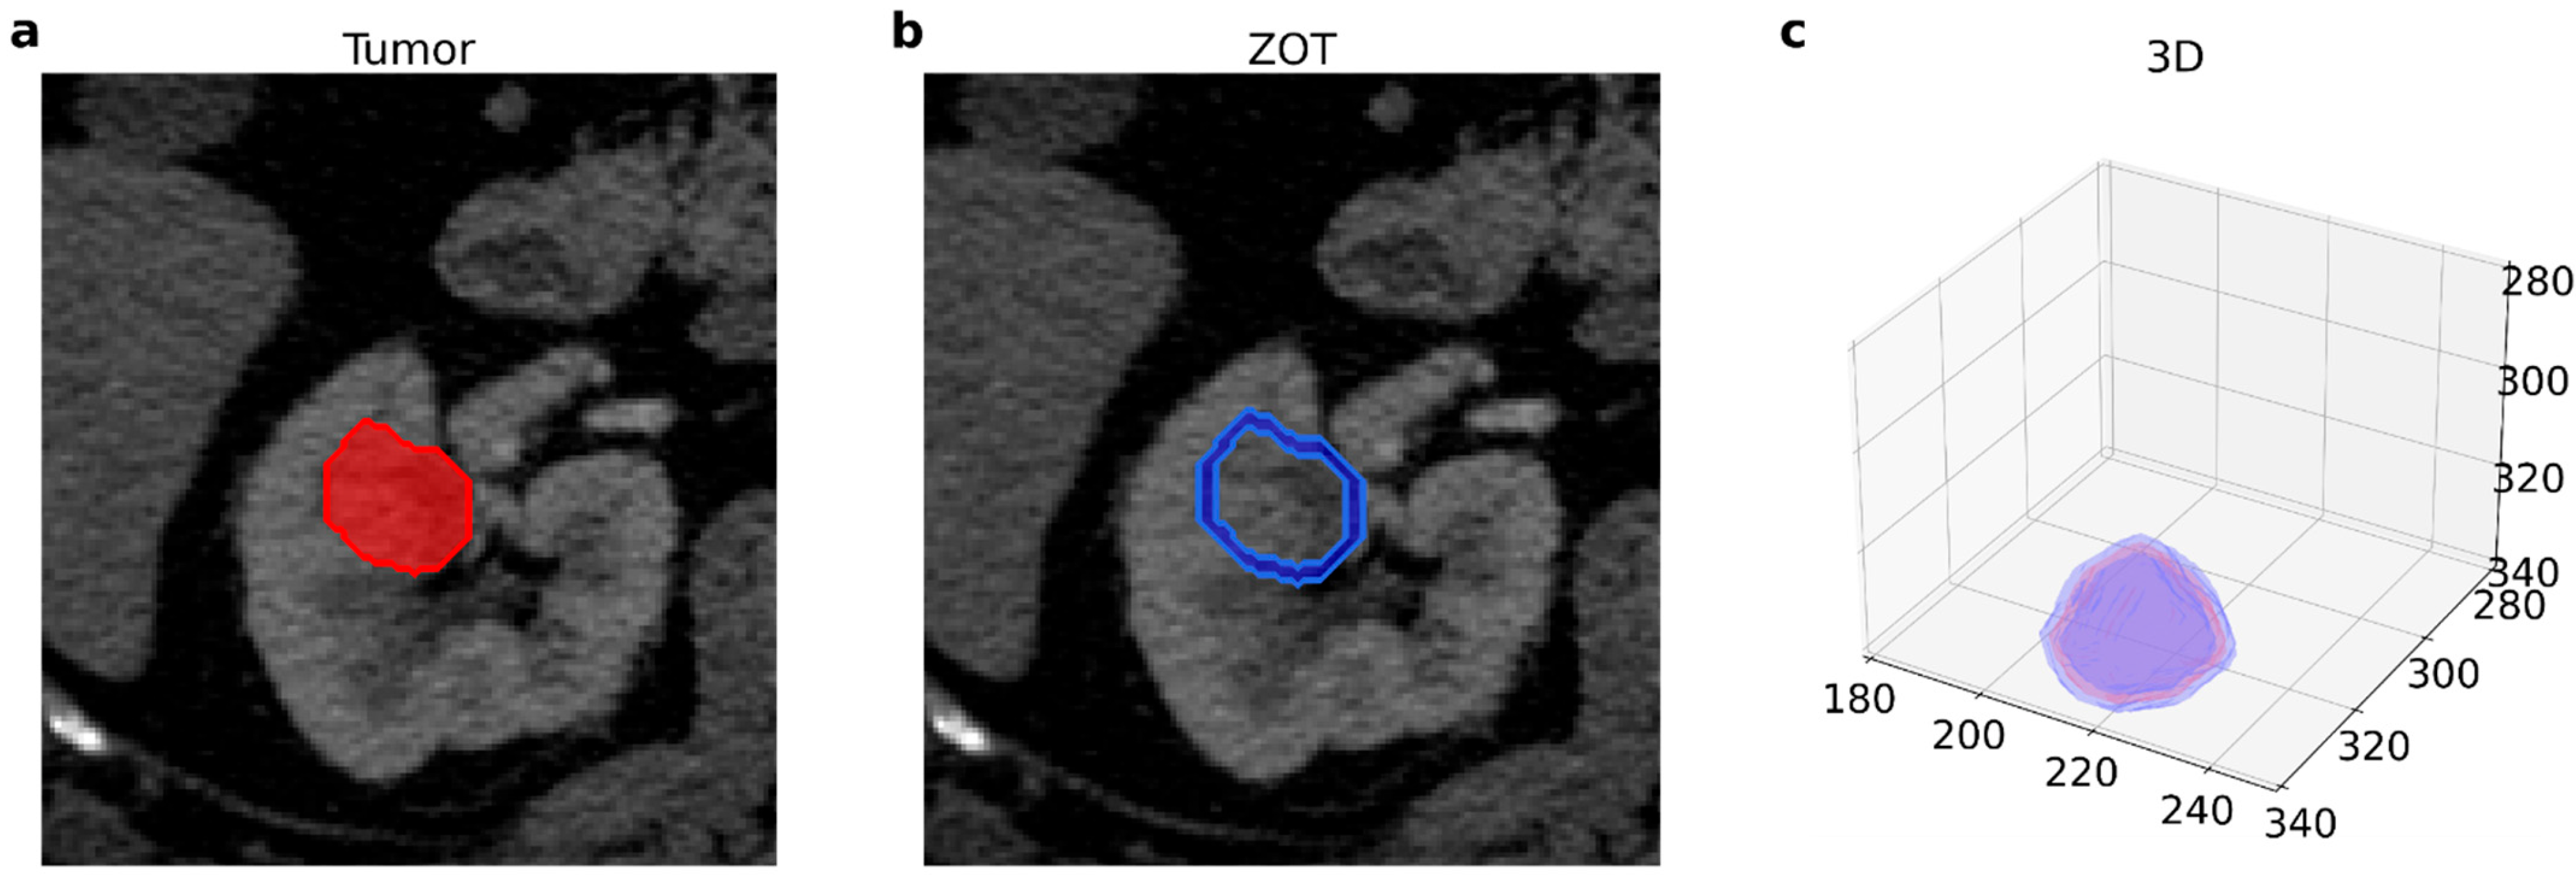

- Renzulli, M.; Mottola, M.; Coppola, F.; Cocozza, M.A.; Malavasi, S.; Cattabriga, A.; Vara, G.; Ravaioli, M.; Cescon, M.; Vasuri, F.; et al. Automatically Extracted Machine Learning Features from Preoperative CT to Early Predict Microvascular Invasion in HCC: The Role of the Zone of Transition (ZOT). Cancers 2022, 14, 1816. [Google Scholar] [CrossRef]

- Zhang, L.; Yankelevitz, D.F.; Henschke, C.I.; Jirapatnakul, A.C.; Reeves, A.P.; Carter, D. Zone of Transition: A Potential Source of Error in Tumor Volume Estimation. Radiology 2010, 256, 633–639. [Google Scholar] [CrossRef]